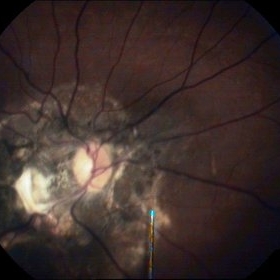

Optic Nerve Head Avulsion

Sep 15 2014 by Mehul A Shah

A 30-year-old male presented with loss of vision following blunt trauma.

Photographer: Drashti Netralaya,Dahod

Imaging device: Zeiss ff450

Condition/keywords: optic nerve head avulsion